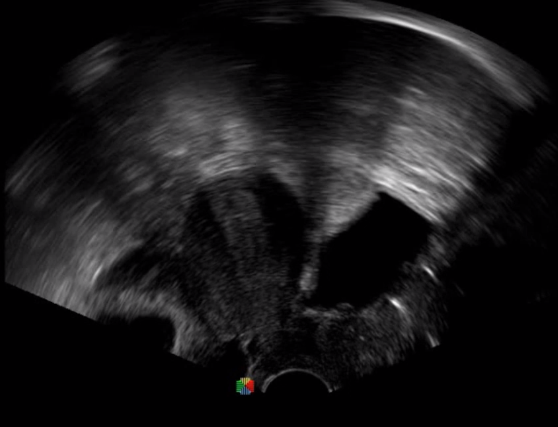

5   TEE

TEE(經(jīng)食道超聲心動(dòng)圖)將超聲探頭置入食道內(nèi),從心臟的后方向前近距離探查其結(jié)構(gòu) ,克服了經(jīng)胸超聲檢查的局限性,避免肺內(nèi)氣體、胸壁脂肪、胸廓畸形等因素影響,觀察角度更多,圖像更加清晰,測(cè)量數(shù)據(jù)更準(zhǔn)確。

經(jīng)食道超聲 大動(dòng)脈短軸